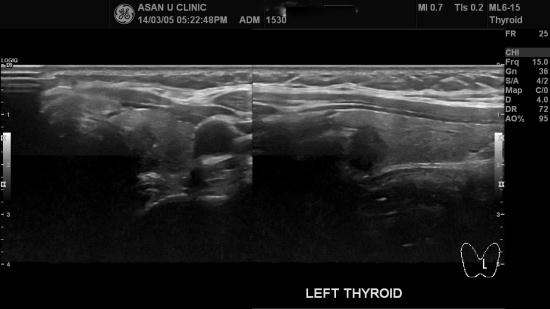

검사하는 김에 하신다고 함께 시행한 갑상선초음파에서 좌엽에 1cm 전후의 혹이 있어

세침흡인검사로 유두암이 진단되셨습니다.